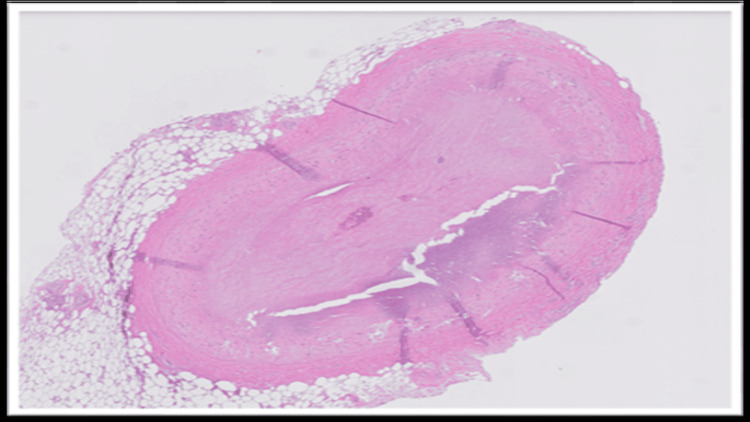

The blood and vitreous fluid were collected for toxicology analysis. Microscopic examination of the heart showed a complete occlusion (100%) of the proximal portion of the left anterior descending coronary artery due to an organized thrombus (Figure 1). A trichrome stain was performed, which showed fibroblastic growth within the thrombus (Figure 2). Elastic stain performed on the section revealed a focus of disruption of the internal elastic lamina (Figure 3). The rest of the anterior descending coronary artery, the left circumflex artery, and the right coronary artery showed normal caliber with no evidence of thrombus or atherosclerosis. A focal area of scarring was identified in the interventricular septum and left ventricle. The right ventricular wall showed a subendocardial scar. No evidence of acute myocardial infarction (e.g., myocyte necrosis, contraction band necrosis, wavy fibers, or early neutrophilic infiltration) was identified in the sections from the right and left ventricles. The abdominal aorta showed no atherosclerotic changes. Sections from the liver showed moderate macrovesicular steatosis. No fibrosis was identified.

In fatal cases of non-atherosclerotic coronary thrombosis, the diagnosis is established primarily through autopsy and postmortem toxicology analysis. Gross examination may not reveal significant atherosclerosis in these cases. Histopathological examination of the coronaries may reveal occlusion of the artery by thrombus. However, the possibility of a postmortem thrombus can be ruled out in such cases by doing ancillary studies like trichrome stain, which confirms fibroblast growth within the thrombus, and elastin stain, which reveals disruption of the internal elastic lamina, thereby favoring antemortem thrombus development. These histopathological findings, along with elevated levels of THC and its metabolites, can help in ruling out other causes of SCD, such as vasculitis or atherosclerosis, and thereby identifying the cause of death.